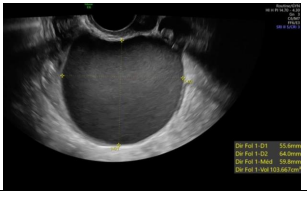

Observe a imagem a seguir.

Sobre as malformações uterinas, os critérios diagnósticos revelados na imagem se correlacionam a qual diagnóstico de malformação mülleriana?